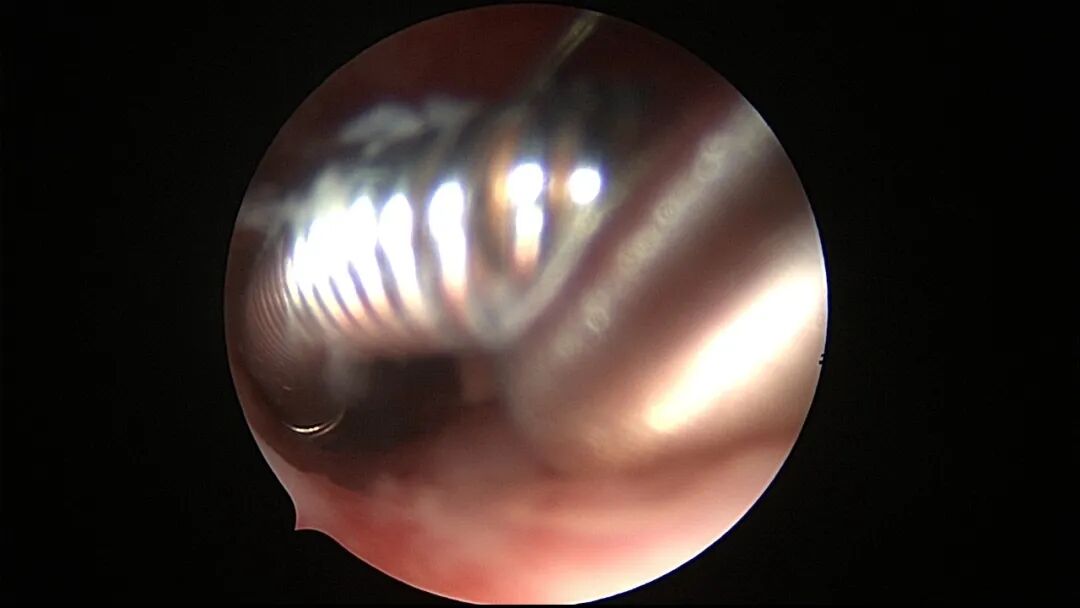

第二次宫腔镜:2021年5月宫腔镜二探取球囊,宫腔形态正常,双侧输卵管开口可见,两侧宫壁见瘢痕,前后壁内膜充血。